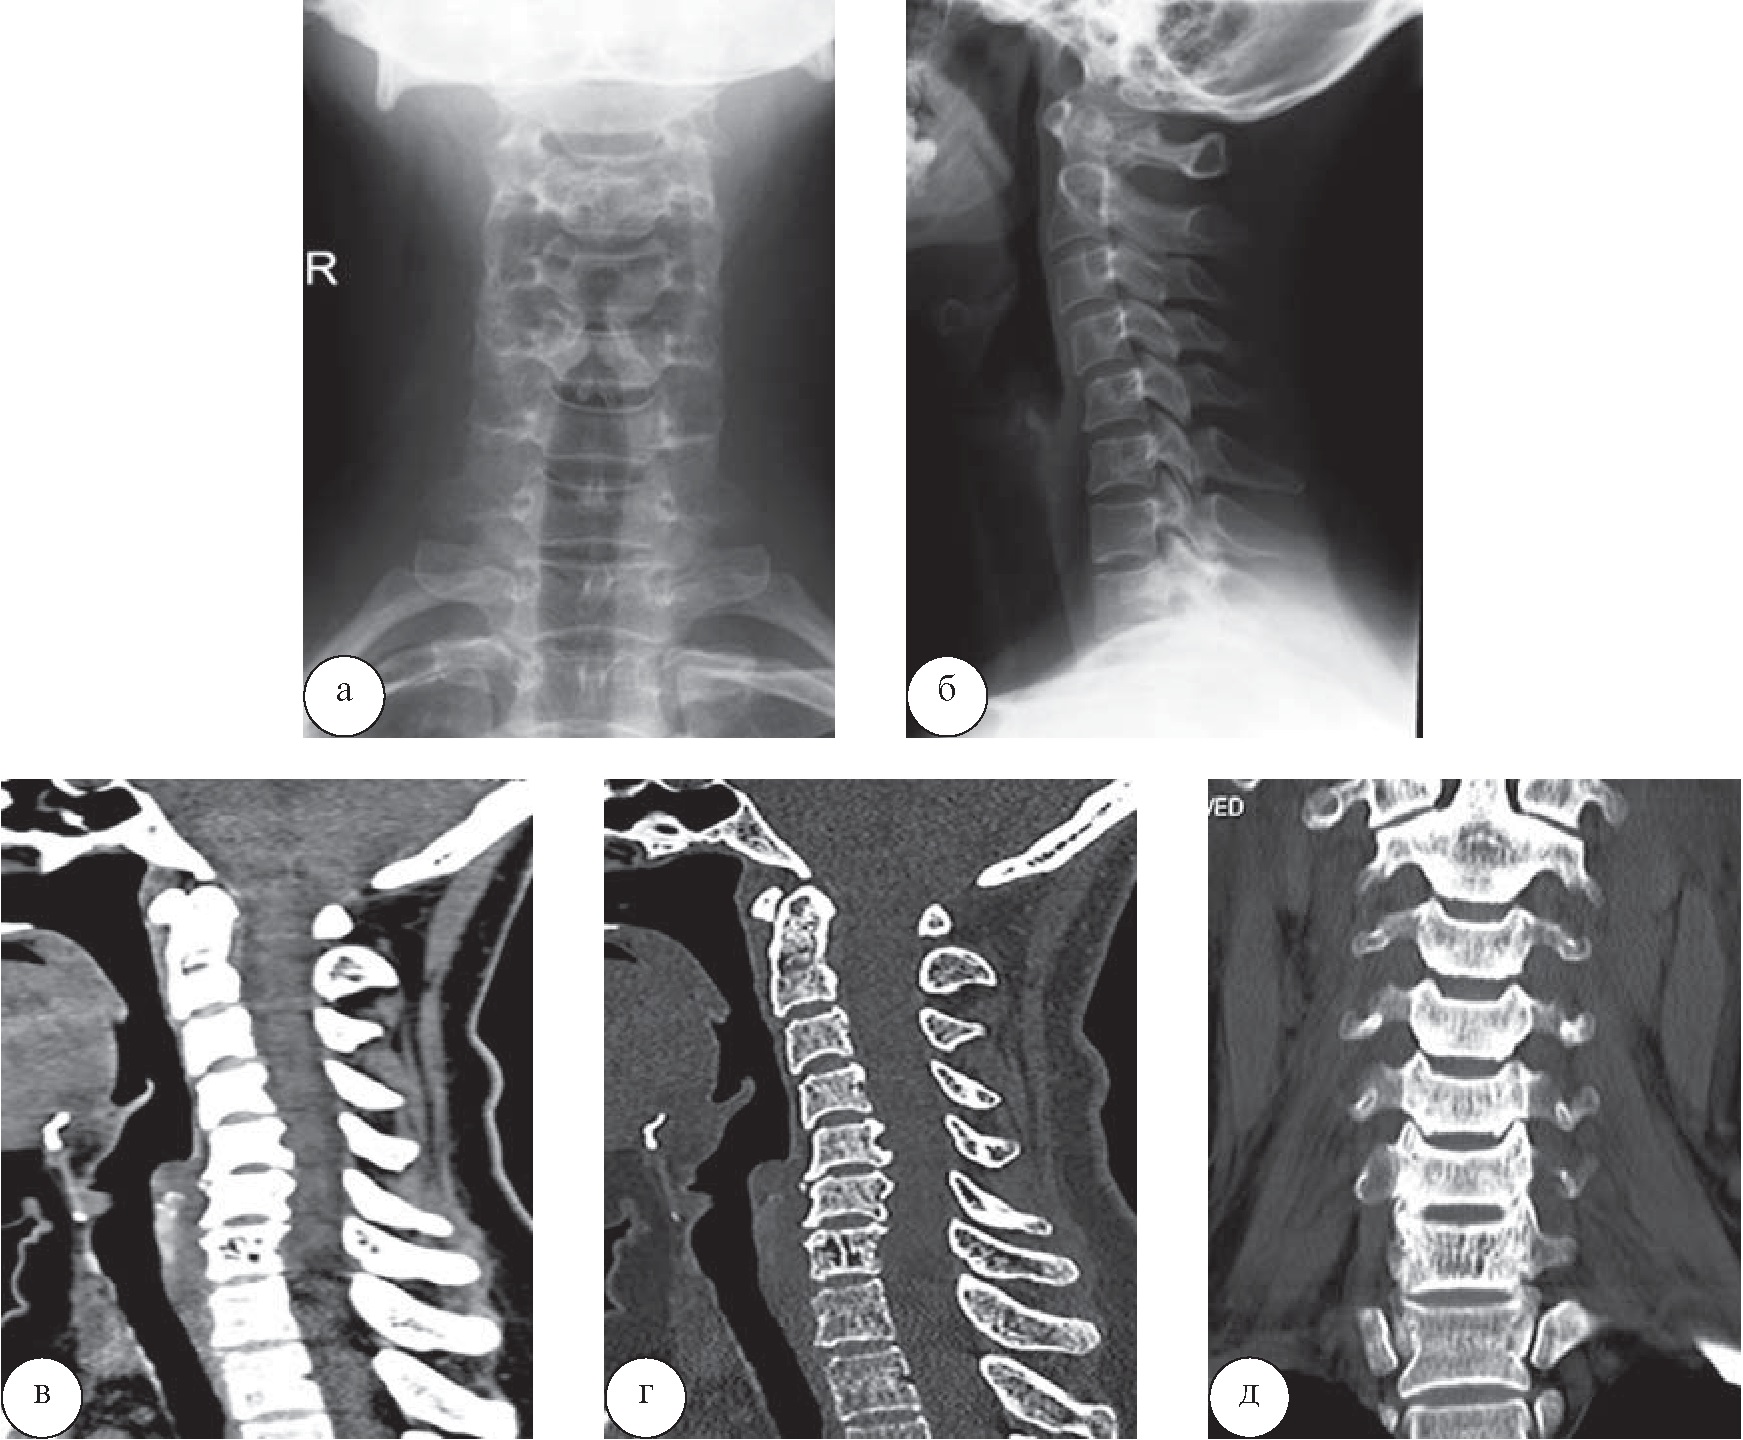

Пациентка 56 лет была направлена на санаторное лечение с диагнозом «остеохондроз» шейного отдела позвоночника, остеоартроз унковертебральных сочленений. У неё при себе и в санаторной карте имелись данные рентгенологического исследования (рис. 4 а, б); КТ была выполнена на базе санатория для оценки степени выраженности и характера дегенеративного процесса (рис. 4, в–д).

Рис. 4. Пациентка К., 56 лет. Рентенограммы шейного отдела позвоночника: а – прямая, б – боковая проекции. Определяются умеренные проявления остеохондроза шейного отдела позвоночника, остеоартроза унковертебральных сочленений. На КТ в сагиттальной (в, г) и корональной (д) плоскостях определяется остеохондроз шейного отдела позвоночника, протрузий межпозвонковых дисков С2–3, С3–4, С4–5, экструзии межпозвонковых дисков С5–6, С6–7, спондилоартроз, гемангиома тела позвонка С7

Наличие крупной гемангиомы в С7 позвонке привело к отмене аппаратной физиотерапии, теплотерапии шейно-воротниковой зоны, мануальной терапии. Дополнительно были назначены лечебная гимнастика в зале ЛФК по щадяще-тренирующему режиму и иглорефлексотерапия.